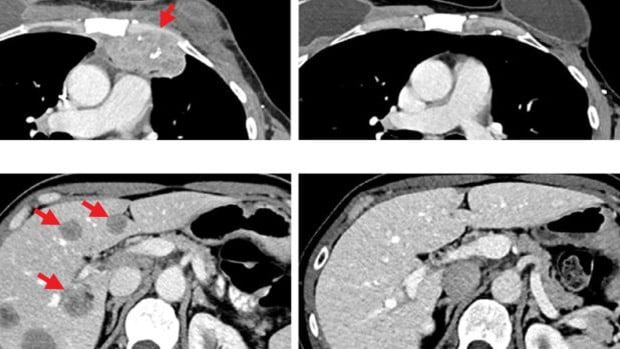

Después de recibir la inmunoterapia, los tumores se redujeron por completo y 5 años después los escaneos muestra que está libre de cáncer.